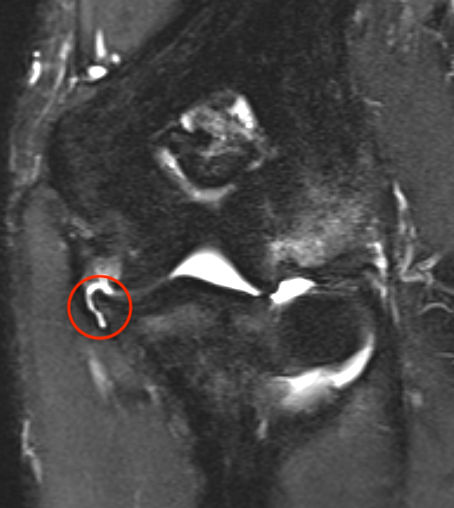

MRI

Bony avulsion UCL complex medial epicondyle

Bony avulsion UCL sublime tubercle

1. UCL repair +/- internal brace -

- if avulsed from medial epicondyle or sublime tubercle

Primary UCL repair with internal brace augmentation

- repair avulsion from medial epicondyle / sublime tubercle as indicated with anchor